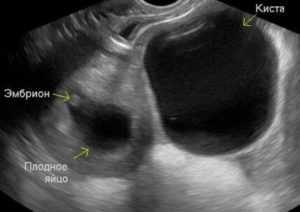

Ниє на ранніх термінах

На початку вагітності дискомфорт в області придатків – звичайне явище. Одна з причин — імплантація плодового яйця. Коли воно закріплюється в матці, то утворює ембріональну нирку і руйнує цілісність кровоносних судин, викликаючи невелика кровотеча і тягнучий біль. Яєчники починають трохи змішатися, так само викликаючи легке нездужання.